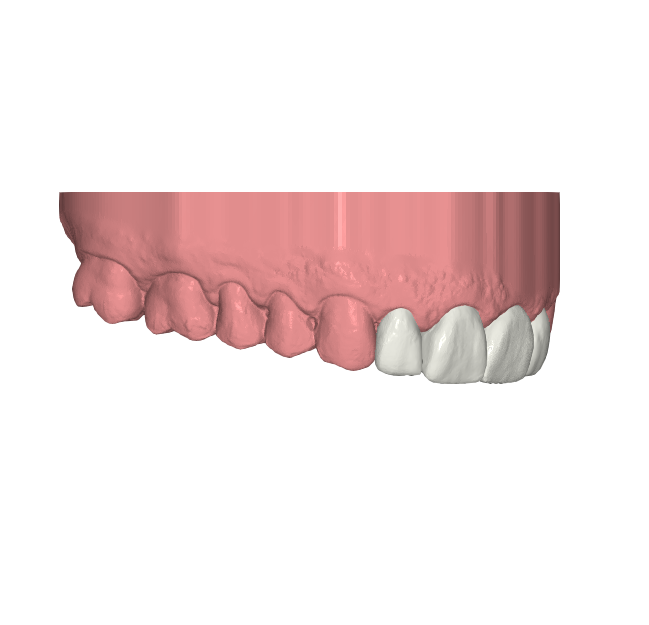

Desde Elevantia Solutions propusimos un Injectable Composite Design con carillas únicamente en esas piezas, para cerrar los espacios sin necesidad de limar sus dientes. Se trabajaron varias versiones del diseño hasta conseguir un resultado totalmente adaptado a sus expectativas, respetando al máximo la estructura dental natural al cerrar los espacios